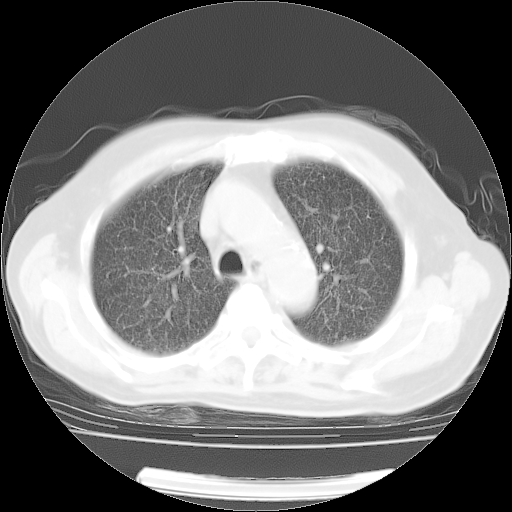

4月14日肺部CT

23.JPG

24.JPG

25.JPG

26.JPG